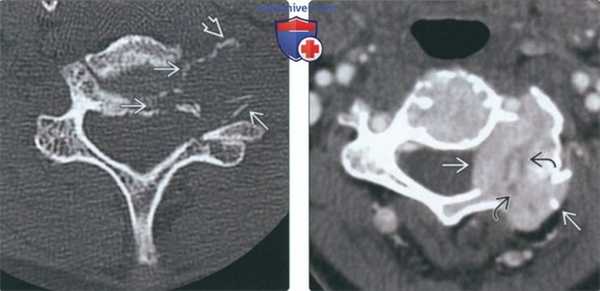

(Слева) На аксиальной КТ без КУ определяется типичный метастаз с деструкцией кости. Не путайте костные фрагменты, напоминающие яичную скорлупу, с опухолевым кальцинатами.

(Справа) На аксиальной КТА определяется мягкотканная опухоль (метастаз рака щитовидной железы) с интенсивным накоплением контраста, свидетельствующим о гиперваскулярности. Мелкие неконтрастирующи-еся очаги в центре представляют собой зоны некроза. Метастазы почечноклеточного рака и меланомы преимущественно являются гиперваскулярными и экспансивными.